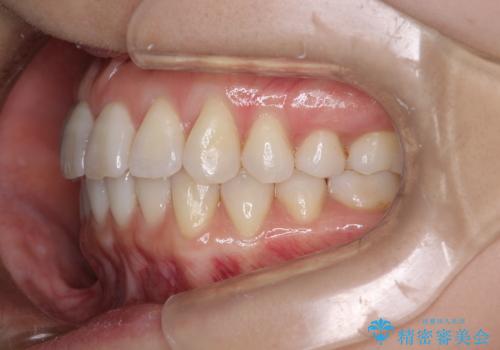

セラミックで歯並びを整えることには限界があります。

また健康な歯を削る必要もあります。

矯正治療は治療期間がかかってしまいますが、不必要に歯を削ることなく、かみ合わせまで考慮して治療が可能です。